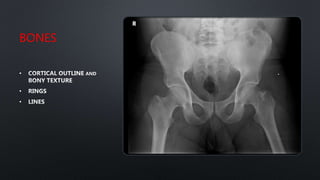

BONES

RINGS

LINES